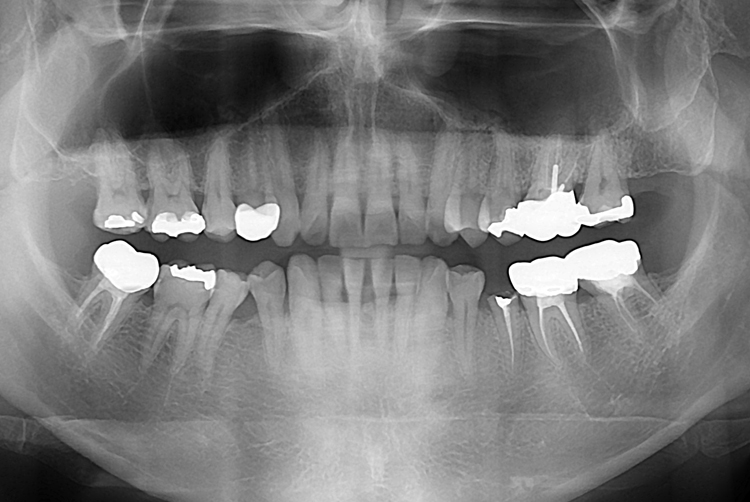

[임플란트] 어금니 임플란트

치료후 : 2019-08-28

세종치과는 많은 환자와 다양한 케이스를 바탕으로

항상 편안한 임플란트 수술을 제공하고자 노력하고,

오래동안 튼튼히 쓸 수 있는 임플란트 수술을 가장 큰 목표로 삼고 있습니다.